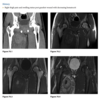

An anteroposterior view of the pelvis

shows flaring of the metaphyseal regions of

the proximal femurs and numerous osteochondromas

arising from the right iliac crest, pubic bones, and proximal right femur (arrows).

Axial CT through upper pelvis - Large right exostosis with soft tissue mass.

AP radiograph of knee - multiple osteochondromas arising from femur and fibula.

DIAGNOSIS: Multiple hereditary exostosis

AD disorder age 10-20s

Signs of malignant transformation - Growth of previous stable exostosis, new or increasing calcifications, new bony erosion

Associated with chondrosarcoma